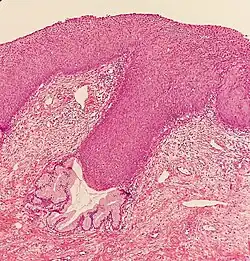

La NCI est classée en grades[14] :

| Grade histologique | Cytologie correspondante | Description | Image |

|---|---|---|---|

| 1 (catégorie I) | Lésion malpighienne intra-épithéliale de bas grade (LSIL) |

|

| 2/3 | Lésion malpighienne intra-épithéliale de haut grade (HSIL). |

| |

| 2 (grade II) |

| ![]() | |

| 3 (grade III) |

| ![]() |